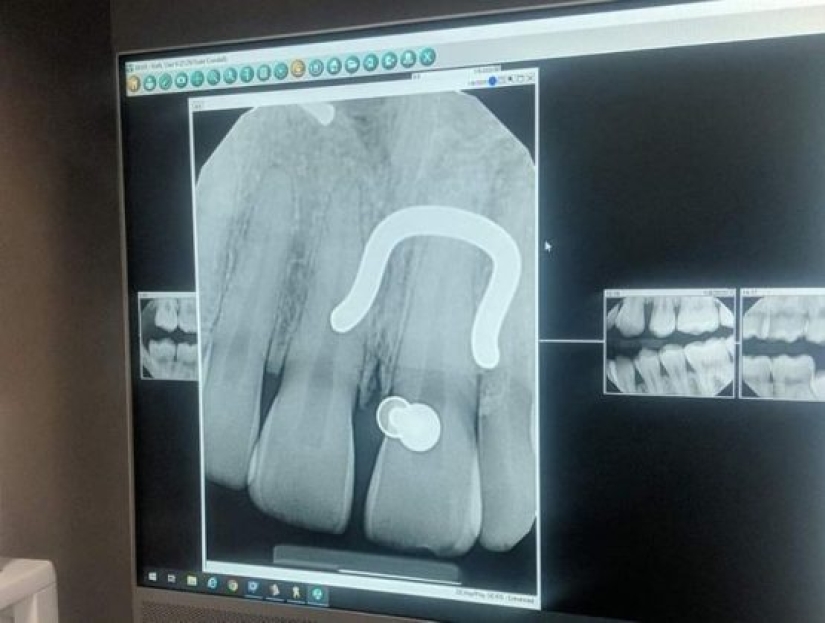

7. "My piercing is x-rayed."